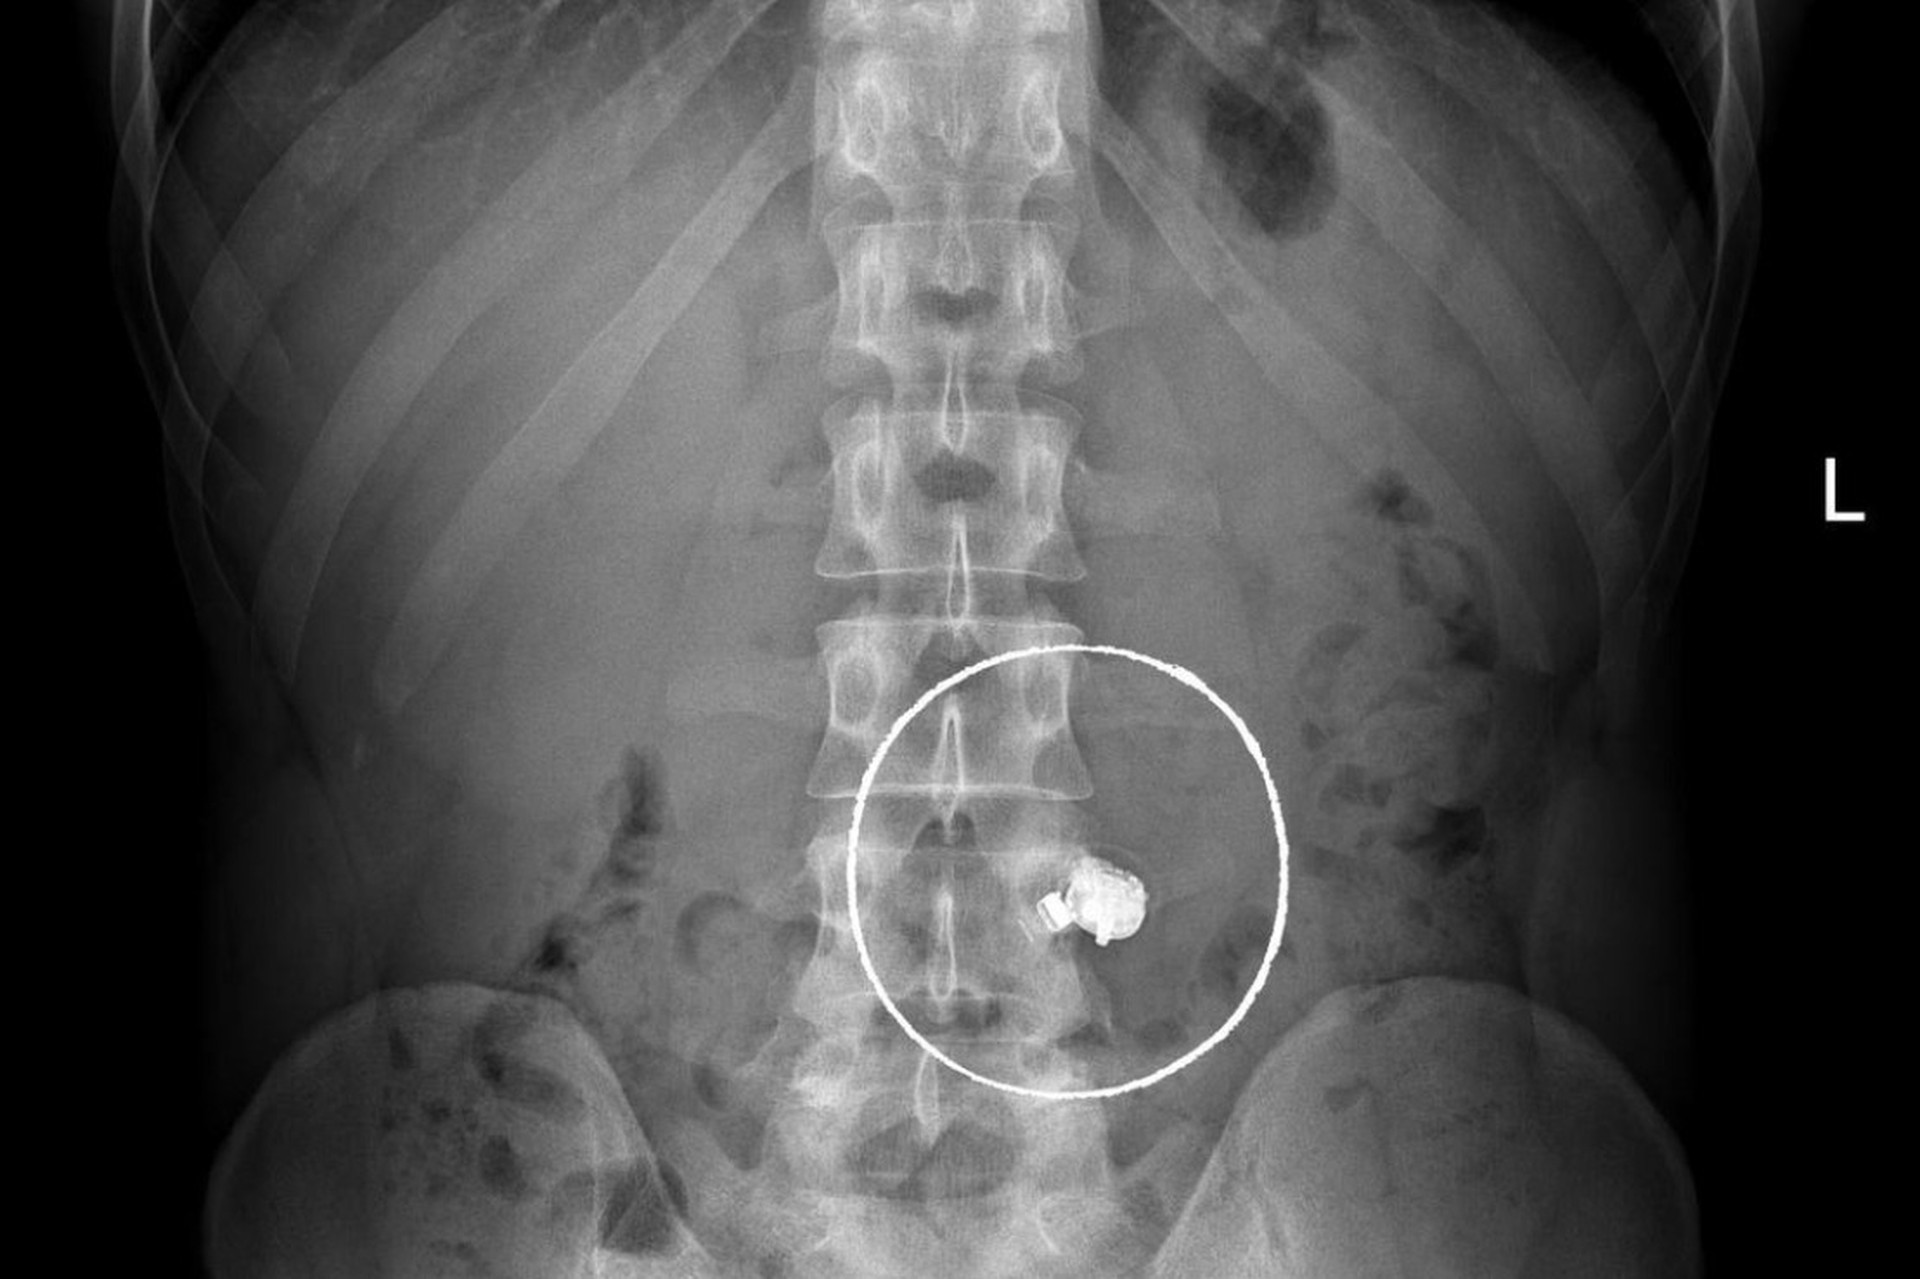

В НИИ скорой помощи им. Н.В. Склифосовского составили топ самых неожиданных предметов, удаленных из пациентов в 2025 году. В списке оказались мелкие гвозди, зубные коронки, Bluetooth-наушники, столовые приборы и даже драгоценности.

«Случаи курьезные, но проблема крайне серьезная – ежегодно в НИИ поступают десятки пациентов с инородными телами. Им требуется экстренная медицинская помощь и зачастую длительное восстановление», – подчеркнули в «Склифе».